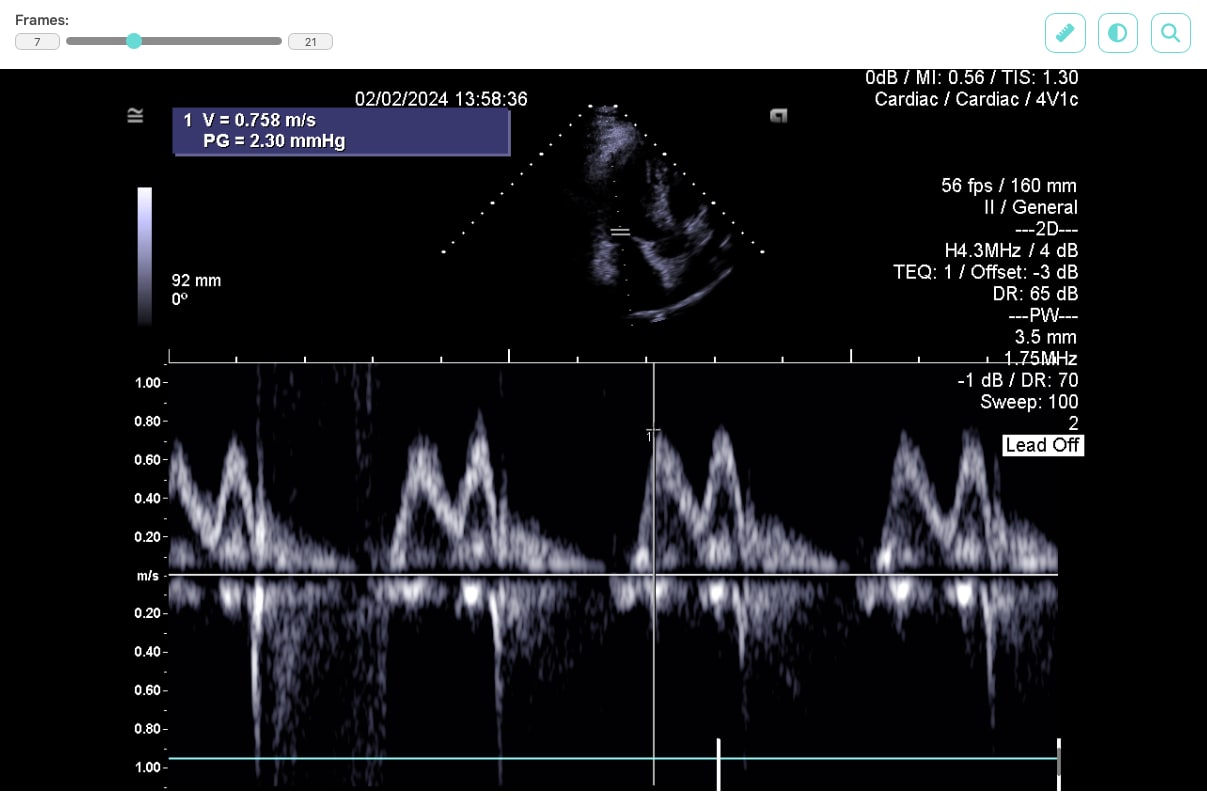

For displaying data on the web, we selected the JavaScript library Cornerstone3D, which not only allows DICOM files to be viewed but also provides features such as adjusting brightness and contrast, or using a ruler to measure distances between displayed parts of the patient’s body.